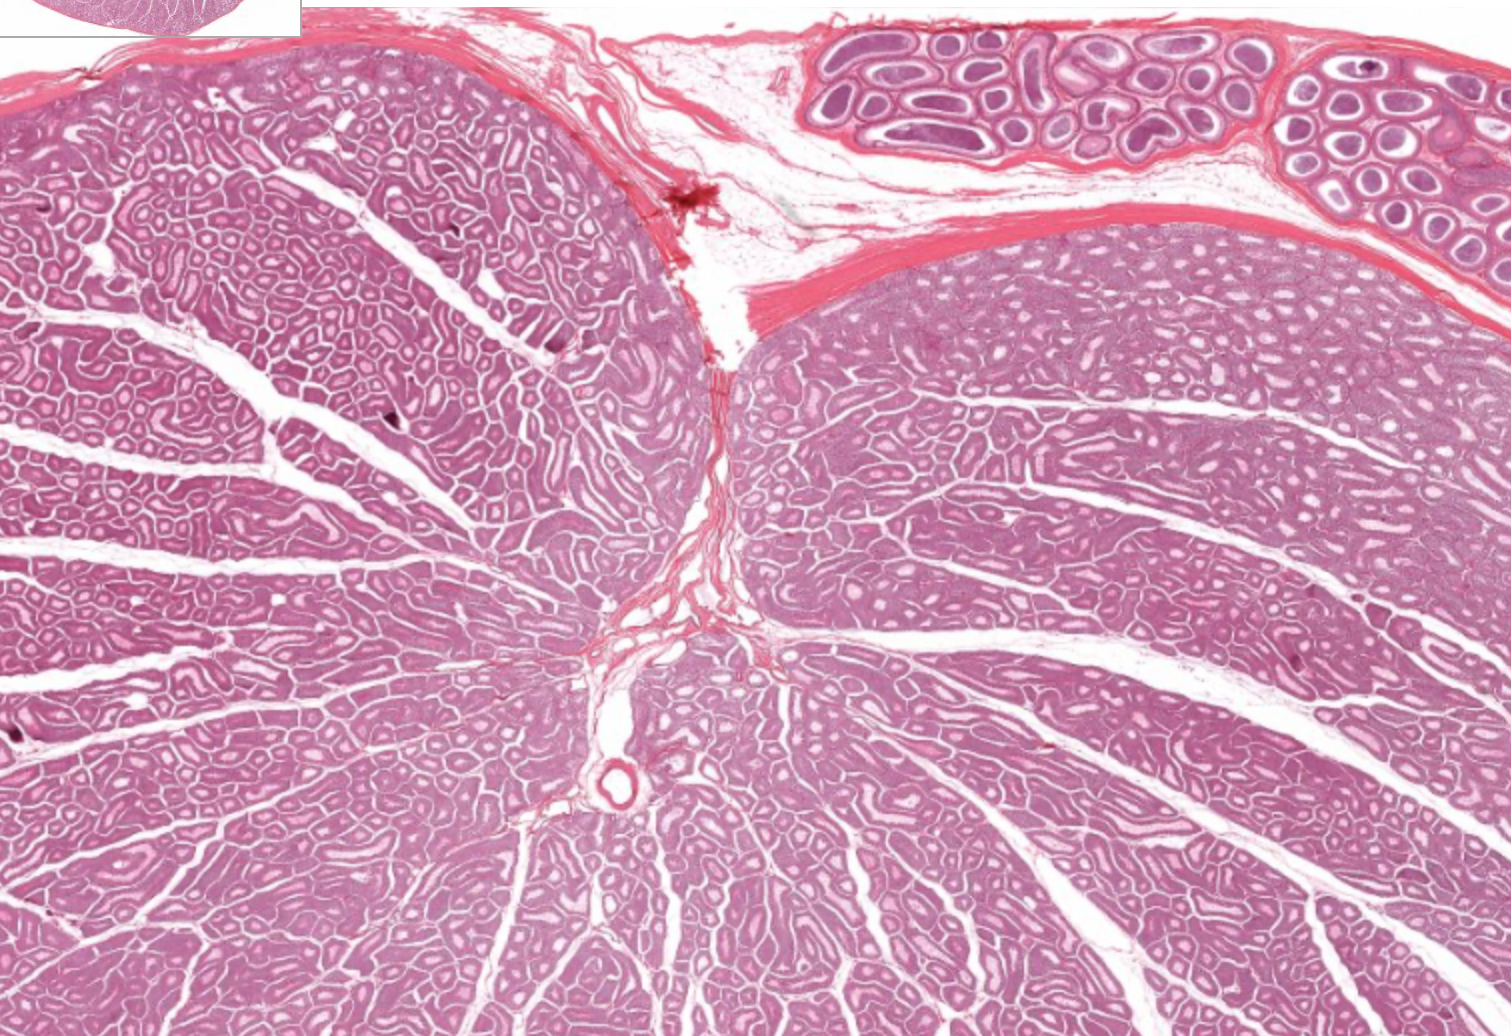

testis

histo

tunica albuginea

tunica vaginalis

seminiferous tubule

lobule

septum

rete testis